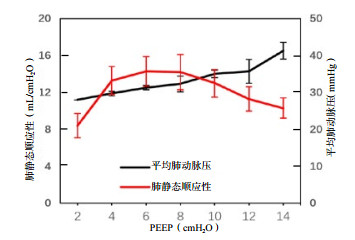

| 图 4 造模后不同PEEP时平均肺动脉压和肺静态顺应性变化 Fig 4 Comparison of MPAP and Cstat at different PEEP after modeling |

造模前后MAP、HR基线水平时差异无统计学意义(P > 0.05),PEEP增加过程中差异无统计学意义(P > 0.05)。造模前后基础状态时SpO2、CVP及MPAP差异均有统计学意义(P < 0.05),是ARDS本身造成的影响。PEEP变化时造模后的SpO2、CVP低于造模前,MPAP高于造模前。PEEP递增时,造模后CVP、MPAP、SpO2变大,MAP先变大后变小,差异有统计学意义(P < 0.05),见表 3。其中MAP在PEEP为14 cmH2O和2 cmH2O时通过事后比较,差异无统计学意义(P > 0.05)。MPAP相对于CVP在PEEP增加过程中增加幅度更为显著。

PEEP增加时TAPSE变化趋势不定,最终变小,CVP、MPAP变大,SV是先变大后变小,以上数据说明右心功能较早出现变化。SV在一定PEEP范围内增大,是由于肺顺应性增加,肺血管阻力降低;随着PEEP继续增大,肺血管阻力增大,SV变小。吸气早期由于跨肺压增加, 胸腔负压增大,使更多肺静脉血液回流, 左心前负荷、右心后负荷增加[21];以及胸腔压力增加导致左心室后负荷下降, 总效应为心脏射血维持不变或略微增加。高PEEP水平时,呼气末由于右心排血量的减少,使左心前负荷下降, 导致左心排血量随之下降。临床上如果忽略此时的变化,没有及时调整呼吸机参数,急剧扩张的右心室会使室间隔左移,使左心室受到压迫,充盈受限,导致心输出量进一步减低,最终发生循环衰竭[22, 24]。虽然PEEP可以使塌陷的肺泡复张,但由于ARDS肺的不均一性,可能造成整体的肺血管阻力增加[25],Enson等[26]提出氧合指数越高,平均肺动脉压越高,导致心输出量下降,本实验结果也验证这一点。Lansdorp等[27]的关于潮气量和顺应性对ARDS患者机械通气时胸内压影响实验,发现大约三分之二的气道压被转移到了胸膜,余下三分之一则转移到心包和上腔静脉,导致上腔静脉压下降及右心房压不变,以上可以解释在PEEP增加时中心静脉压反应性不如肺动脉压,故监测肺动脉压变化更为重要。本实验选择TAPSE作为右心室收缩功能监测指标,主要是因其重复性好,容易获取,比较少受到其他因素影响,被美国心脏超声协会推荐作为右室收缩功能评估指标之一。但本实验结果TAPSE反应性不理想,一是与犬基础心率快有关,且犬心脏小,为心脏超声测量增加了难度;二是犬的心脏与人的心脏超声有区别,但这不影响其成为临床上监测右心功能指标之一[28-29]。